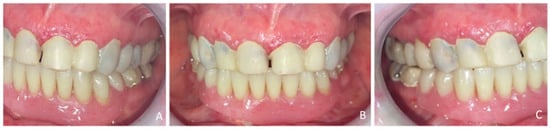

Figure 5.

Transitional prosthetic treatment with composite resin mock-up and mandibular transitional partial denture occludes arch’s view: (A) right view, (B) front view, (C) left view.

2.4.1. Step 1: Diagnostic Set-Up and Provisional Prosthesis

A diagnostic tooth set-up was created, including a 3 mm increase in occlusal vertical dimension (OVD). It was validated to confirm esthetic and functional outcomes. A transitional removable partial prosthesis (RTPP) was fabricated for the mandible. The OVD was increased using a composite resin mock-up (Voco StructurPremium, Cuxhaven, Germany) applied to all remaining teeth. Adjustments were made to refine the shape of the maxillary anterior teeth. A definitive mandibular impression was taken with polysulfide material (Permlastic, regular body, KaVo Kerr) using a custom tray, and maxillomandibular records were obtained with a wax baseplate. One week later, a 10-tooth RTPP (replacing 45, 44, 43, 42, 41, 31, 32, 33, 34, and 35) was inserted. The provisional prosthetic phase required three clinical sessions (Figure 5).